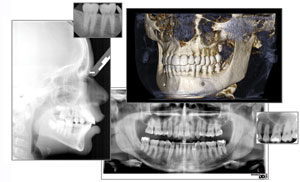

John Steck: “Gendex has a long history of providing panoramic devices. Seizing the opportunity to partner with i-CAT, the company was able to take advantage of the i-CAT-developed 3D technology that is very popular with dentists. Since Gendex historically has been very well known and trusted by general practitioners, the GXCB-500™ 3D system was developed with these particular dentists in mind—for implants, extractions, third-molar extractions, impacted teeth, restorations, endo—all things that would provide better clinical results and expansion of procedures to GPs, as well as oral surgeons and periodontists. This 2-in-1 unit is extremely flexible, with capability for both panoramics and 3D, and it is adjustable to capture from the bottom of chin to base of sinus cavity, and extending to the TMJ. Later in 2011, we are anticipating a new high-quality pan/ceph/3-D combination system with many projections and the ability to capture 3D from a single tooth to the full arch or the TMJ. The system will deliver what GPs need: repeatability in the capture and quality of panoramic images and scans, flexibility to capture the images necessary for the procedures they perform, and the ability to upgrade to ceph and/or 3D as the practice grows.”